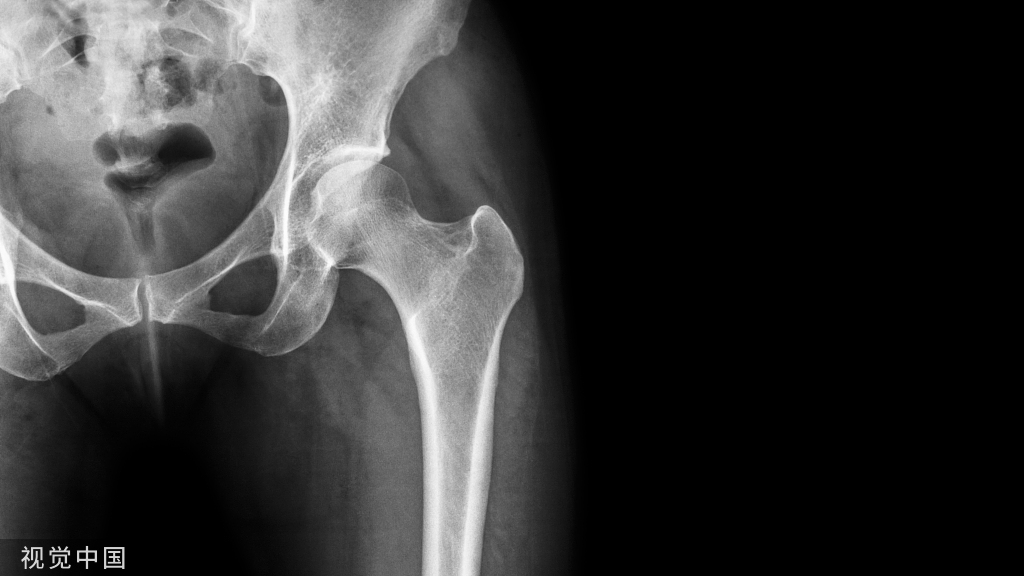

重建术后双束图

重建术后X片